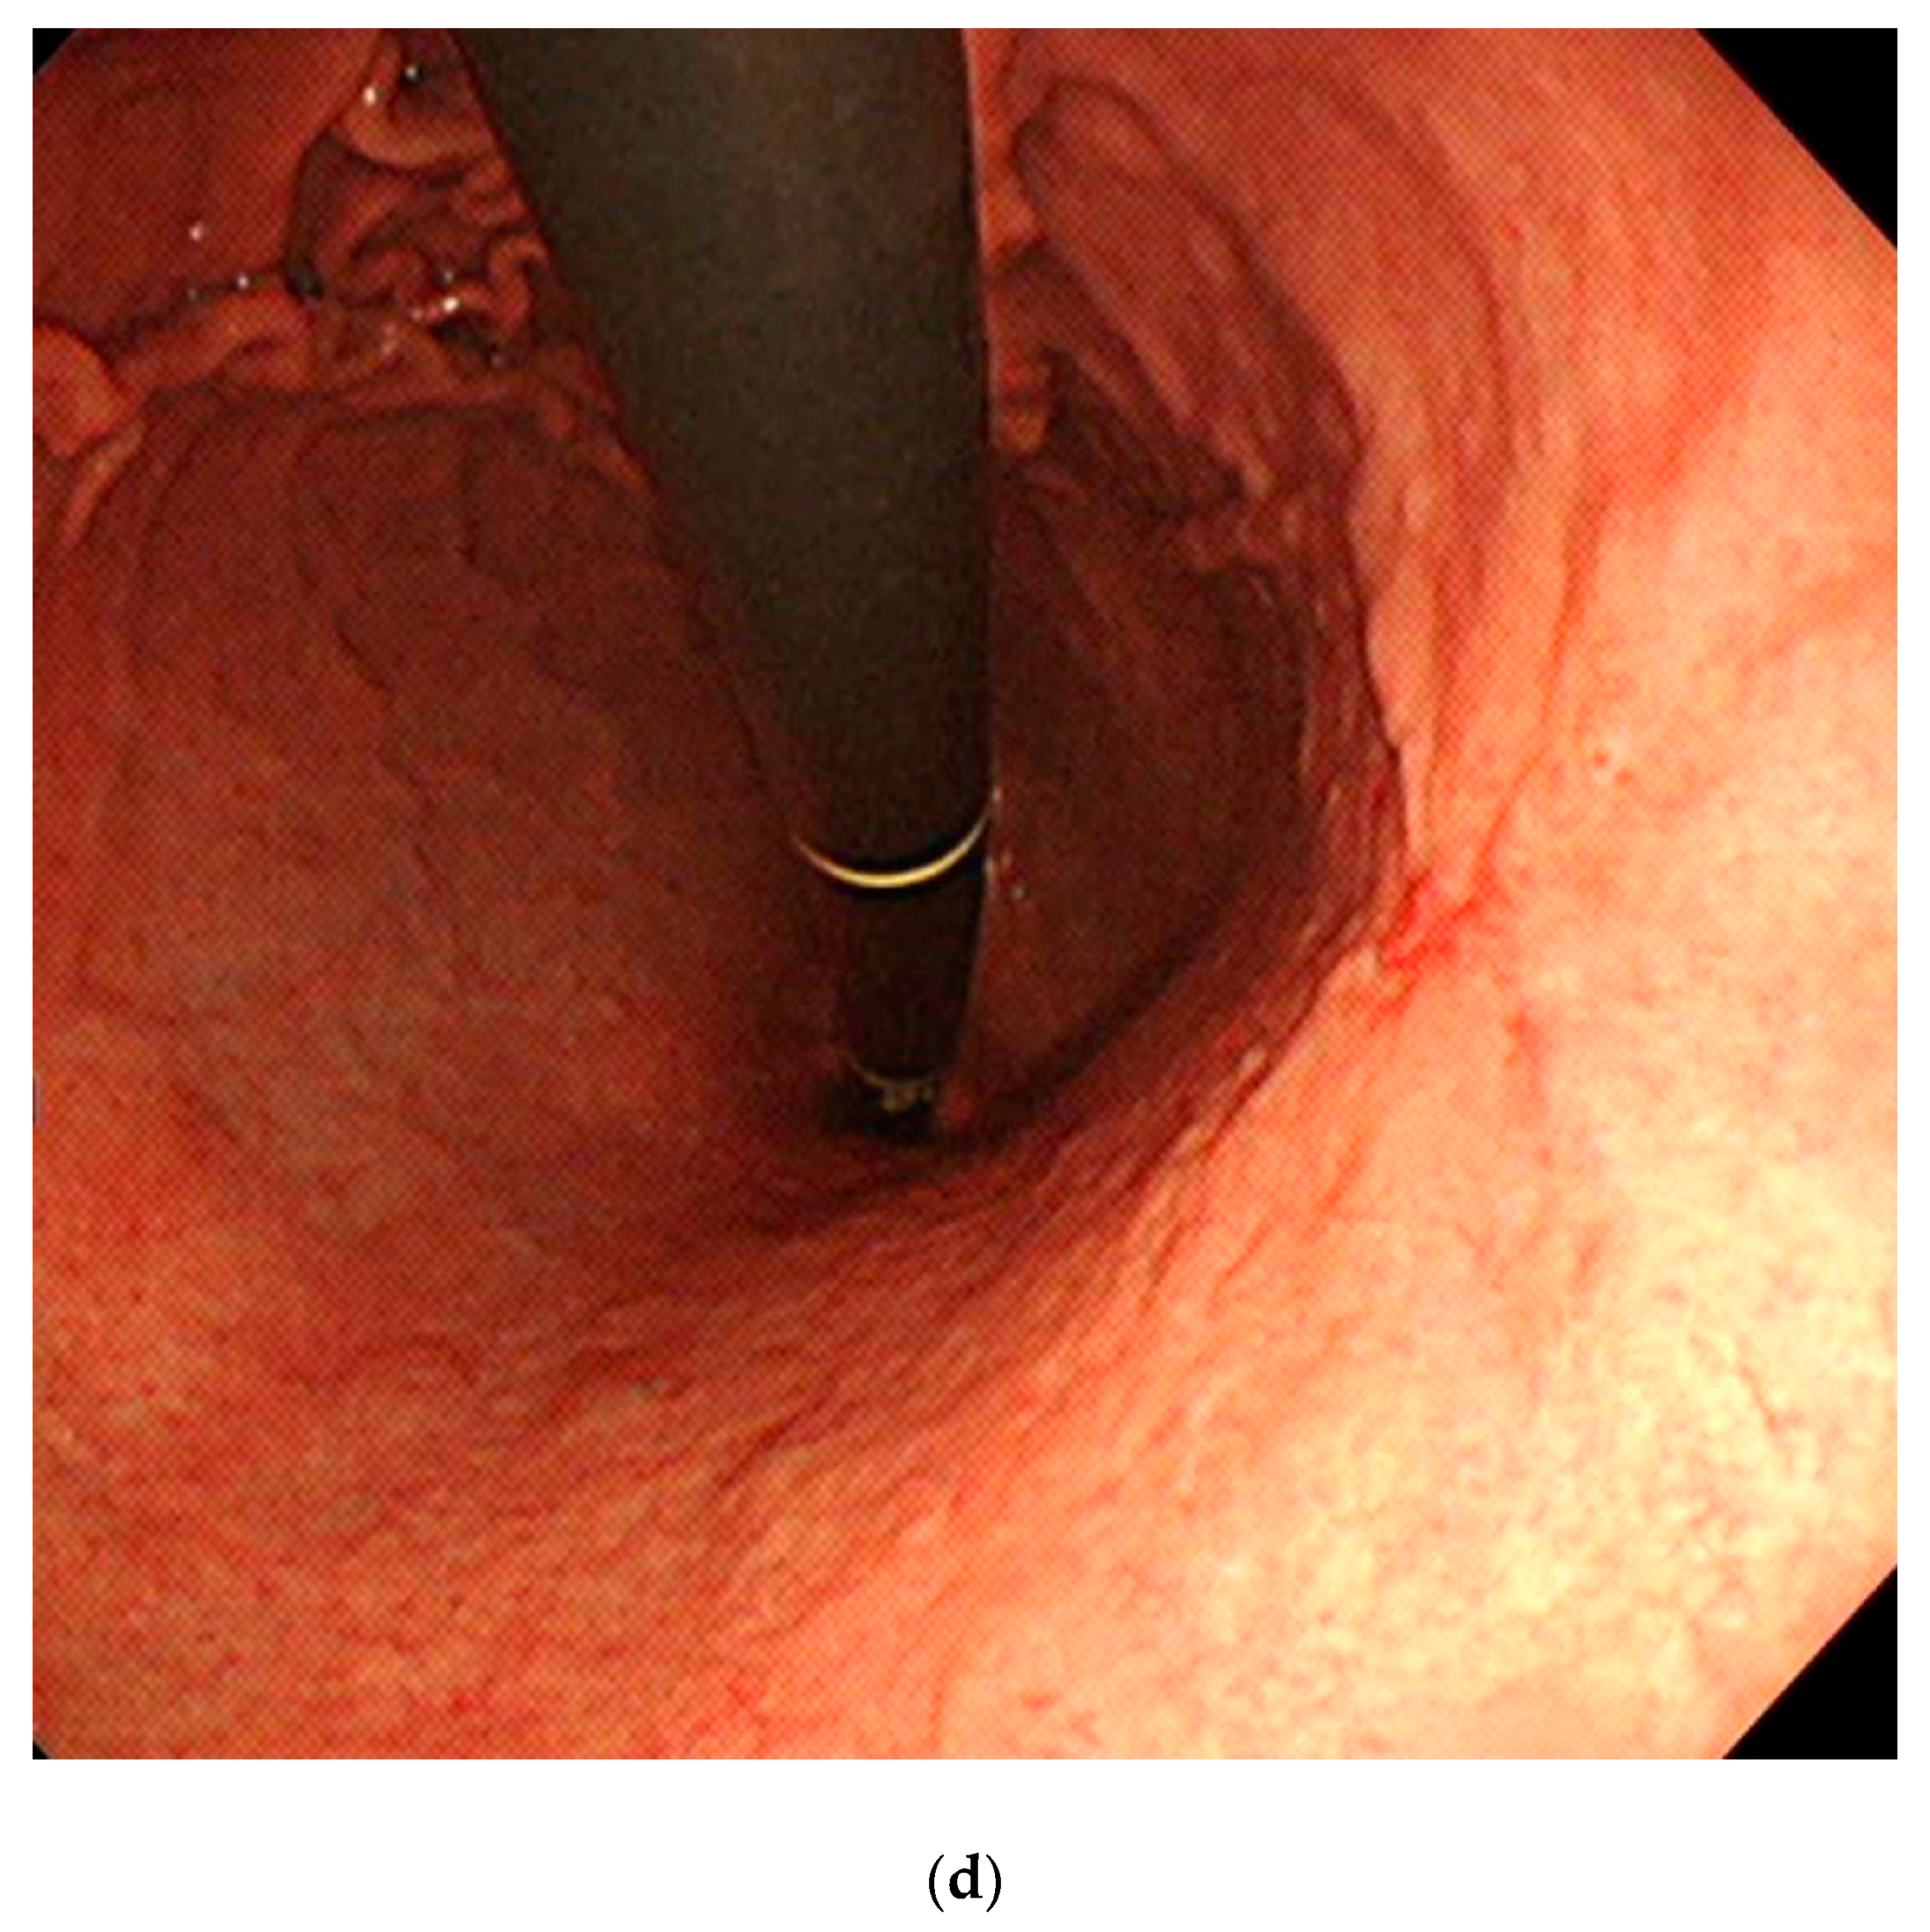

3.5. Attention Maps